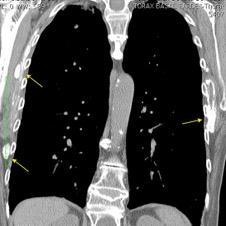

Nódulo en língula.

Cirugía de Ca .de mama hace 23 añosedema de brazo y ganglio en axila. ¡Metástasis!.